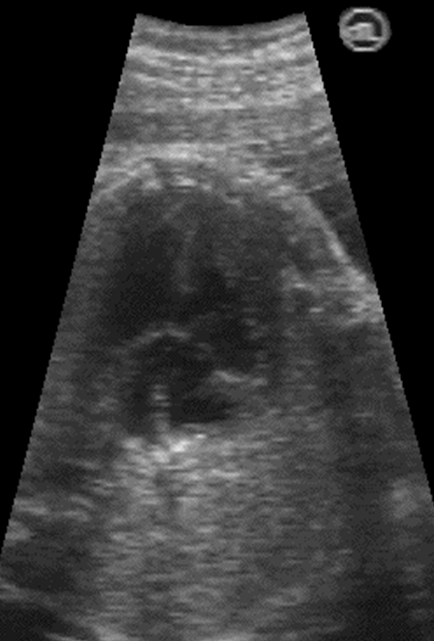

What is Hypoplastic Right Heart?

Underdeveloped right heart from obstructed RVOT

Secondary to pulmonary stenosis

Hypoplastic Right Heart will have multiple structures that are small, what are they?

Tricuspid valve

Right ventricle

Pulmonary artery

Hypoplastic Right Heart